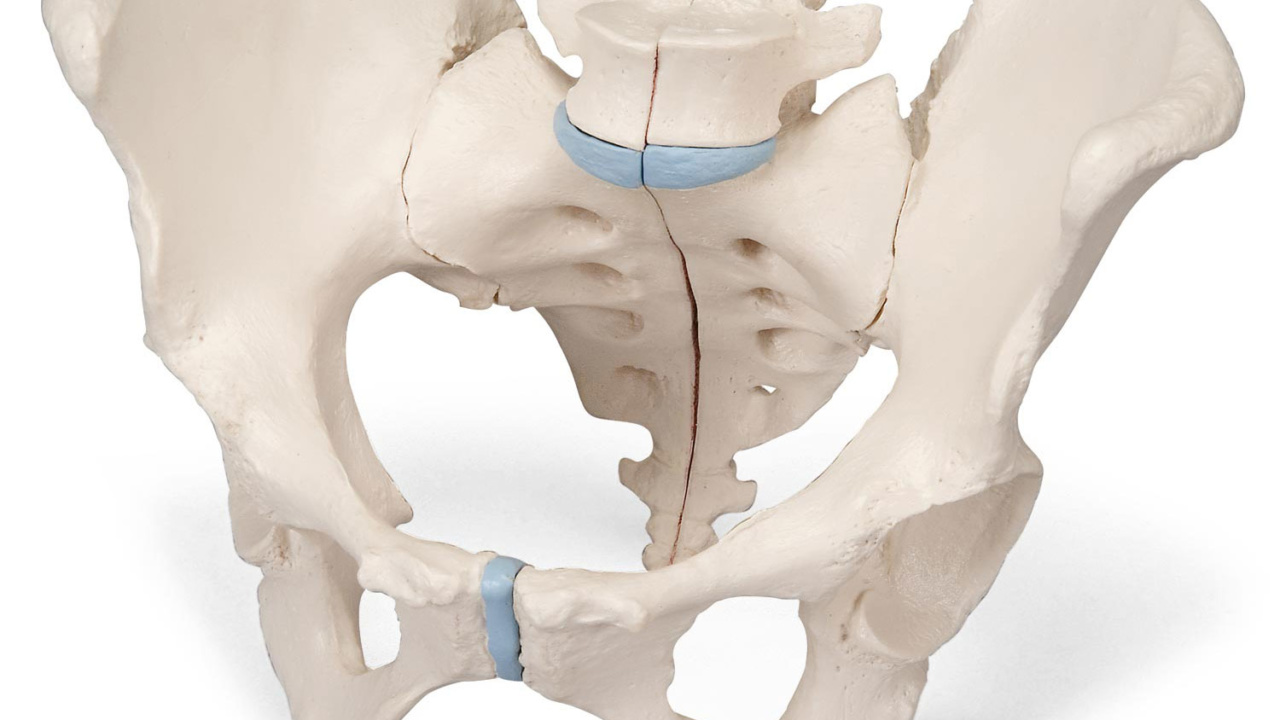

人体模型 骨盤模型 女性 子宮 解剖学的詳細 Amazon | 女性骨盤モデル - 生殖器・血管・神経・筋肉・子宮の詳細なの詳細情報

Amazon | 女性骨盤モデル - 生殖器・血管・神経・筋肉・子宮の詳細な。Amazon.co.jp: 女性 骨盤と 子宮模型 筋肉解剖学 女性骨盤 骨盤底筋と。子宮の解剖模型 - 3480 - GPI Anatomicals - 卵巣の / 実習用 / 女性用。解剖学的詳細を再現した人体模型、頭部と首部が観察可能。- モデル: 人体模型- 部位: 骨盤 大腸 子宮 腹部- 特徴: 解剖学的詳細が再現された構造- 素材: プラスチック製- サイズ: 約30cmの高さご覧いただきありがとうございます。絵画用に模型を購入しましたが使用をしないままでしたのでお譲りします⭐︎とても丁寧な作りでおすすめです◎。h20-1-1280x720.jpg。